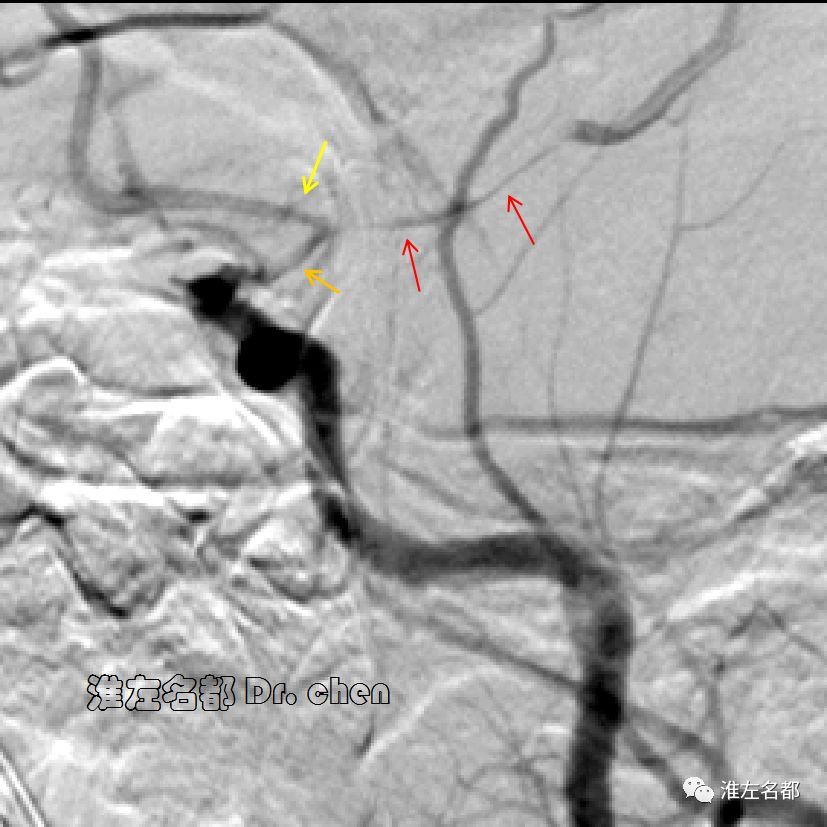

△管壁高分辨MRI(增强T1-SPACE):左侧大脑中动脉主干管壁未见异常(橙箭),左侧颈内动脉远端管壁增厚和强化(红箭)。

△管壁高分辨MRI(增强T1-SPACE):左侧颈内动脉末端检测到夹层“内膜征”(橙箭)。